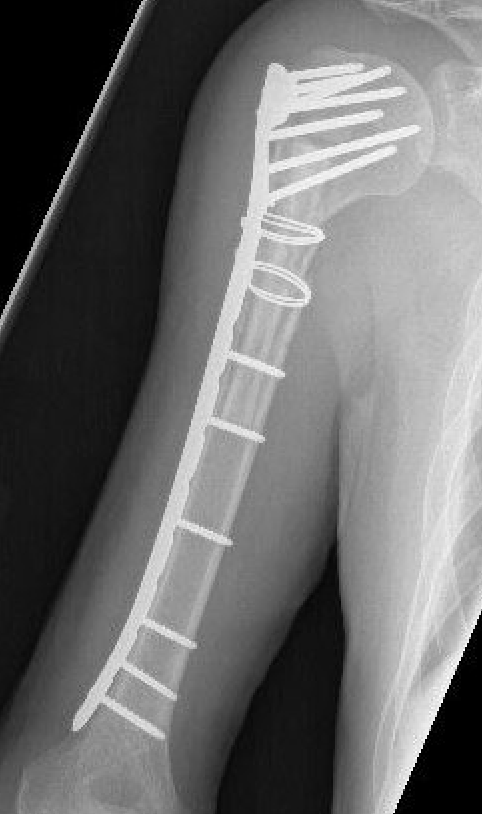

Minimally Invasive Plate Osteosynthesis (MIPO)

Concept

Bridge plating

Indirect fracture reduction

Anterior plating with narrow 4.5 mm LCP

Lateral plating with long proximal humerus plate

Narrow LCP plate

Precontour narrow LCP plate

- subtle convex curve proximally

- subtle concave curve distally

- 10 - 15 degrees internally rotated